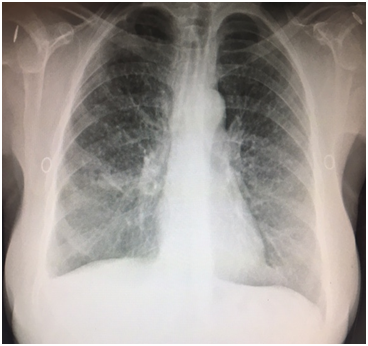

A 57 year old Caucasian female was admitted for dry cough, fever, loss of appetite and chest pain for three weeks. She had a history of tonsillectomy, ankylozing spondylitis, uveitis, pelvis fracture and tibia fracture. Her father died of colonic carcinoma. Her mother had hypertension and previous pulmonary tuberculosis. The patient was under treatment with certolizumab, methotrexate, and prednisolonefor ankylozing spondylitis and uveitis. Daily 300mg isoniazid was also given simultaneously with certolizumab for prophylaxis. Initial laboratory findings revealed WBC 8.2X103/mm3, hemoglobin 10.8g/dl, platelets 341X103mm3, lymphocytes 1.4X103/mm3, creatinine 0.74mg/dl, AST 18IU/L, ALT 18IU/Lmm3, LDH 167IU/L, albumine 3.56gr/dl, CRP 18.6 mg/dl, and calcium 9.1 mg/dl. ECG showed sinus ryhtm. Tuberculin test was negative. Chest x-rayshowed diffuse miliary nodules, alveolar infiltration in the right lower lobe, and right pleural effusion (Figure 1). Pleural protein 4.57g/dl, LDH 353U/L, and albumin 3.56g/dl. Pleural fluid had 1540cells/mm3 with a 74% lymphocyte ratio. Pleural fluid ADA was 114U/L (normal 0-40 U/L). The pleural fluid was exudative compatible with tuberculosis. Computed tomography of the thorax revealed diffuse miliary nodules, infiltration in the right anterior segment of the lower lobe, and right pleural effusion (Figures 2-4). Sputum stains was positive for acid-fast bacilli. Mycobacterium tuberculosis was isolated from the sputum culture. The final diagnosis was miliary tuberculosis associated with certolizumab occuring on the third month of treatment. The patient was commenced on pyrazinamide, isoniazid, rifampicine, and ethambutol treatment for tuberculosis while certolizumab treatment was stopped.

Figure 1 Chest x-ray showing diffuse miliary nodules and right pleural effusion.

The patient had a negative tuberculin test and a normal chest x-ray before certolizumabtreatment. She was commenced on prophylactic isoniazid treatment because the patient had an exposure to active tuberculosis. Miliary tuberculosis with pleural effusion and right lower lobe infiltration occured on the third month of treatment. The patient had an appropriate screening for tuberculosis including medical history, tuberculine test, and chest x-ray before anti-TNF-α treatment was started. The sensitivity of the tuberculine test may have been restricted or diminished by the previous immunosuppressive treatment in our patient. The normal chest x-ray before treatment had also a low diagnostic yield for revealing sequela of past or current infection. Following treatment the right lower anterior segment infiltration was only identified at the computed tomography coronal image and was not detected in chest x-ray.